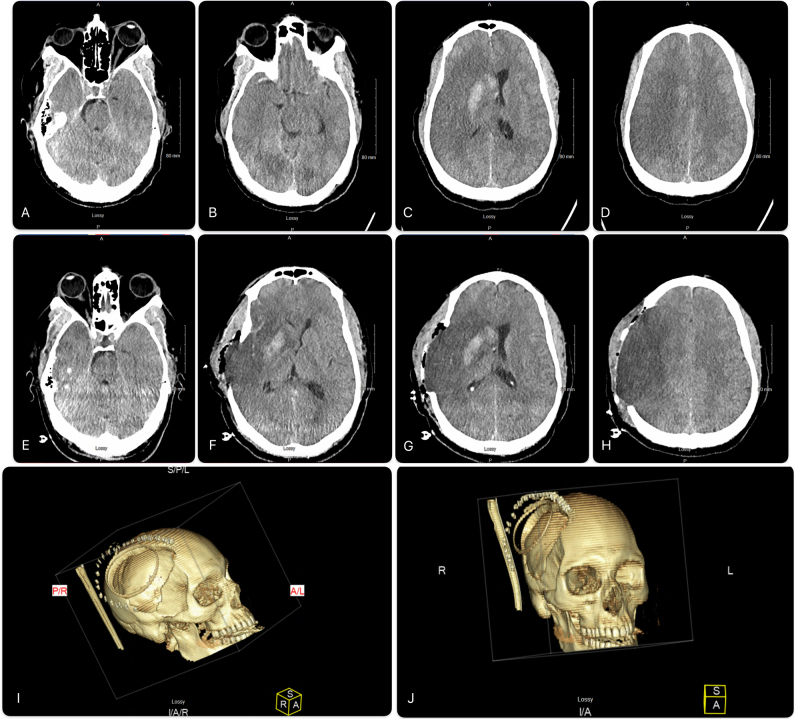

背景:恶性大脑中动脉(MCA)梗死导致脑水肿,可导致脑疝和死亡。标准治疗包括减压性半颅切除术(DHC)和综合神经危重症护理。尽管采取了这些措施,一些患者的病情仍会继续下降。重新开放头皮切口可能允许额外的减压,并提供死亡率的好处。观察:一名47岁男性在静脉溶栓和不成功的机械取栓后发生恶性右MCA区域梗死。尽管积极的高渗治疗和大DHC,患者继续表现出临床衰退和脑水肿的影像学进展。因此,重新打开头皮切口以促进最大程度的脑外疝,作者认为这是治疗脑肿胀的关键策略。在此期间,考虑到暴露的脑表面和潜在的脑脊液泄漏相关的感染风险增加,患者继续使用预防性抗生素。脑肿胀消退后,行右半球部分切除术切除梗死半球。值得注意的是,在干预和延长的康复期后,患者取得了显著的功能恢复。经验教训:本病例突出了恶性脑梗死手术治疗中遇到的复杂性,特别是当标准减压措施失败时。https://thejns.org/doi/10.3171/CASE2523。

Observations: A 47-year-old man developed malignant right MCA territory infarction following intravenous thrombolysis and unsuccessful mechanical thrombectomy. Despite aggressive hyperosmolar therapy and a large DHC, the patient continued to exhibit clinical decline and radiological progression of cerebral edema. In response, the scalp incision was reopened to facilitate maximal external cerebral herniation, a strategy the authors believe was critical in managing the brain swelling. The patient was maintained on prophylactic antibiotics during this period, given the increased infection risk associated with exposed brain surface and potential CSF leakage. Following the resolution of cerebral swelling, a right partial hemispherectomy was performed to excise the infarcted hemisphere. Notably, the patient achieved significant functional recovery following the intervention and an extended period of rehabilitation.